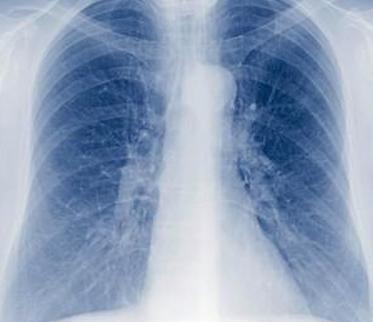

Пневмония у недоношенных детей: осложнение недостаточной функции легких

Недоношенные, у которых респираторные проблемы возникают как осложнение при ранних родах, подвергаются большему риску развития легочных инфекций, таких как пневмония. У недоношенных младенцев не только инфекция, вызванная пневмонией, вызывает проблемы, но и воспаление, вызванное инфекцией, может также сокращать воздушное пространство, в котором происходит обмен кислорода и углекислого газа. К счастью, это состояние не является чем-то необычным, поэтому его легко обнаружить и лечить. Первичное лечение пневмонии у недоношенных детей — это дополнительный кислород и, что не менее важно, антибиотики, чтобы убить инфекцию.